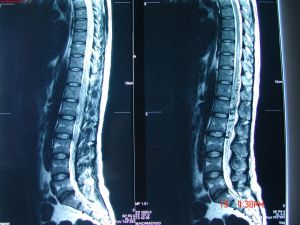

脊髓栓系綜合徵CT圖診斷檢查

脊髓栓系綜合徵影像脊髓栓系綜合徵的診斷依據:①疼痛範圍廣泛,不能用單一根神經損害來解釋;②成人在出現症狀前有明顯的誘因;③膀胱和直腸功能障礙,經常出現尿路感染;④感覺運動障礙進行性加重;⑤有不同的先天畸形,或曾有腰骶部手術史;⑥MRI和(或)CT椎管造影發現脊髓圓錐位置異常和(或)終絲增粗。

1.MRI是診斷脊髓栓系綜合徵最佳和首選的檢查手段。它不僅能發現低位的脊髓圓錐,而且能明確引起脊髓栓系綜合徵的病因。

2.CT椎管造影CT脊髓造影能顯示脂肪瘤、脊髓圓錐、馬尾神經和硬脊膜之間的關係,對制訂手術入路有指導作用。另外,CT能顯示骨骼畸形、脊柱裂、椎管內腫瘤等。但是CT診斷脊髓栓系綜合徵的敏感性和可靠性不如MRI,CT椎管造影又屬有創性檢查,因此,對典型脊髓栓系綜合徵病人,MRI診斷已足夠。由於MRI和CT各有其優缺點,對複雜脊髓栓系綜合徵或MRI診斷可疑者,還需聯合套用MRI和CT椎管造影。